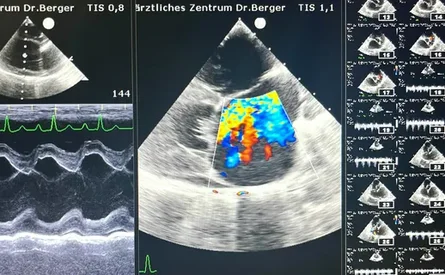

Für die Diagnostik und Behandlung stehen in unserem Fachzentrum hochwertige Geräte zur Verfügung:

• Herzultraschall (Echokardiografie mit Farbdoppler) Phillips CX-50 USG